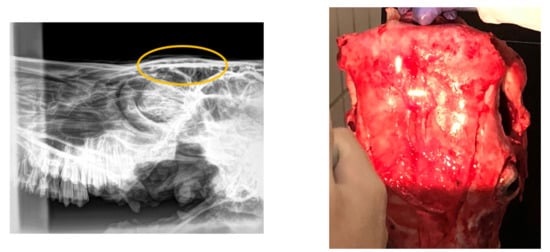

Regarding the radiographical study, it was observed that the skulls presented rating 1 “no visible damage” (70%) or 2 “indentation no cracking” (20%), and rating 3 “indentation with cracking but no displacement” (10%) following the Malaysia Standard (Figure 3, Figure 4, Figure 5). Consequently, 90% of the HSS animals (ratings 1 and 2) would be accepted for halal commercialization. However, no radiographical differences existed between ratings 1 and 2 (Figure 3 and Figure 4); only macroscopic differences in soft tissues were noted.

Figure 3.

Digital radiography rating 1 (following Malaysia Standard 1500:2009), and related photograph.

Figure 4.

Digital radiography rating 2 (following Malaysia Standard 1500:2009), and related photograph.

Figure 5.

Digital radiography rating 3 (following Malaysia Standard 1500:2009). The eclipsed area defines the perimeter of the damaged area. On the right is shown the related photograph.

As Majeed et al. [37] exposed, a beating heart is indispensable for a thorough bleed-out by the animal and attainment of a higher amount of blood at exsanguination is better during halal slaughter according to Shari’ah (halal law). Even if the variation in Islamic jurisprudence is one of the primary determinants of intra-regional trade of halal meat import demand in OIC member countries [38], most certifiers indicate that they accept pre-slaughter stunning if the stunning does not result in the death of animal prior to exsanguination, a Muslim should perform the slaughter and a short prayer must be recited and only manual (by hand) slaughter is acceptable [39]. According to this premise, our findings revealed the halal slaughter with stunning was the best procedure from the microbiological and AW point of view. At present, the Malaysian Protocol for the Halal Meat and Poultry Productions allows the non-penetrative captive bolt stunning for bovine [22] setting a rating scale of 6 grades depending on the skull damage. The radiological study in our research demonstrates the benefits of this stunning method in the tested animals, evidencing the ratings 1 or 2 for 90% of the skulls; this means the halal condition for the carcass.